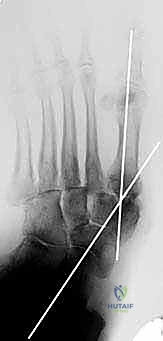

2. الأشعة السينية الحاملة للوزن (Weight-bearing X-rays): لتقييم الانهيار العظمي.

هذه هي الخطوة الأكثر دقة. يقوم الدكتور هطيف بإعادة العظام إلى وضعها التشريحي الطبيعي لاستعادة القوس الطولي للقدم، والتأكد من أن باطن القدم أصبح مسطحاً وقابلاً لتحمل الوزن مستقبلاً دون التسبب في تقرحات.

يتم استخدام أسلاك توجيهية (Guide Wires) يتم إدخالها تحت توجيه الأشعة السينية المباشرة (C-arm) من خلال عظام مشط القدم، مروراً بمفاصل منتصف القدم، وصولاً إلى عظام الرصغ (مثل العظم الزورقي أو الكاحل). بعد التأكد من المسار الصحيح، يتم استخدام مثقاب خاص، ثم تُدرج المسامير المحورية الصلبة (غالباً مسامير بقطر 6.5 مم أو 7.0 مم) لضغط المفاصل وتثبيتها بقوة هائلة.